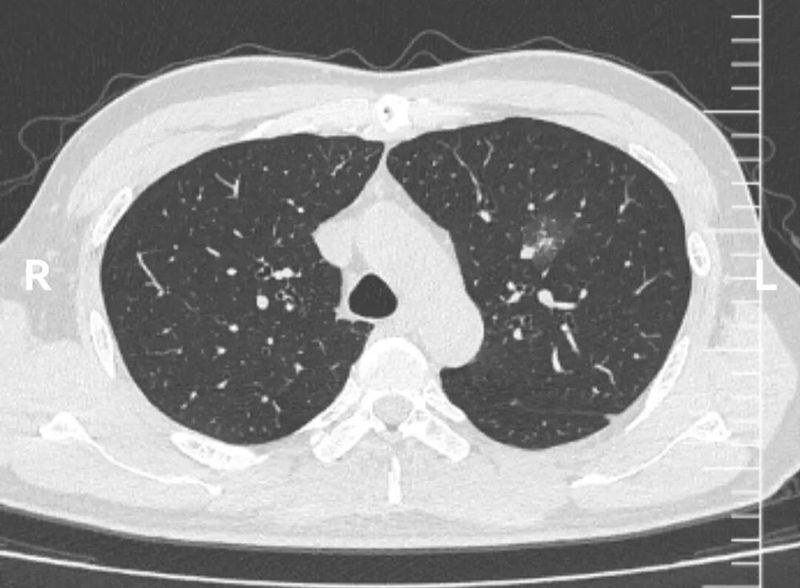

CT图像

这个左上肺混杂磨玻璃结节CT图像非常有特点,首先,磨玻璃成分为主,而且磨玻璃成分边界模糊不清。这本身就是炎症的典型表现。其次,实性成分的形态边界比较清楚,没有分叶、血管异常等形态。